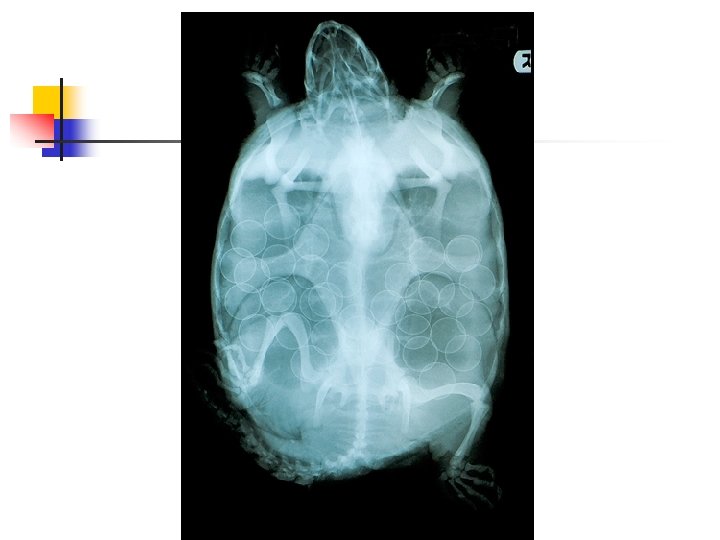

n n This snapping turtle was brought in after it had been hit by a car. Fortunately the injuries were minor and easily treated. She was diagnosed as pregnant, so she was released where she had been found as soon as possible so that she could lay her eggs. Can you count how many eggs?